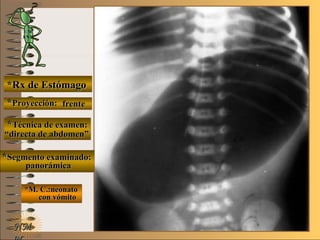

*Rx de Estómago*Rx de Estómago

**Proyección:Proyección:

**Técnica de examen:Técnica de examen:

**Segmento examinado:Segmento examinado:

*M. C.:neonato*M. C.:neonato

con vómitocon vómito

frentefrente

““directa de abdomen”directa de abdomen”

panorámicapanorámica

A-A-El examen es normal o patológico?El examen es normal o patológico?

Examen patológico de estómago sinExamen patológico de estómago sin

contraste (directa) en proyección decontraste (directa) en proyección de

B-B-La patología es congénita o adquirida?La patología es congénita o adquirida?

Patología congénita en neonato; verPatología congénita en neonato; ver

Clasificación General UNTClasificación General UNT

C-C-Puede describir la o las imágenes patológicas?Puede describir la o las imágenes patológicas?

**OpciónOpción

Se identifica una “burbuja” única que se ex-Se identifica una “burbuja” única que se ex-

tiende oblicuamente desde hipocondrio izquier-tiende oblicuamente desde hipocondrio izquier-

do hasta flanco derecho y ocupa la región um-do hasta flanco derecho y ocupa la región um-

bilical determinado por una atresia de píloro;bilical determinado por una atresia de píloro;

nótese la sonda naso-gástricanótese la sonda naso-gástrica